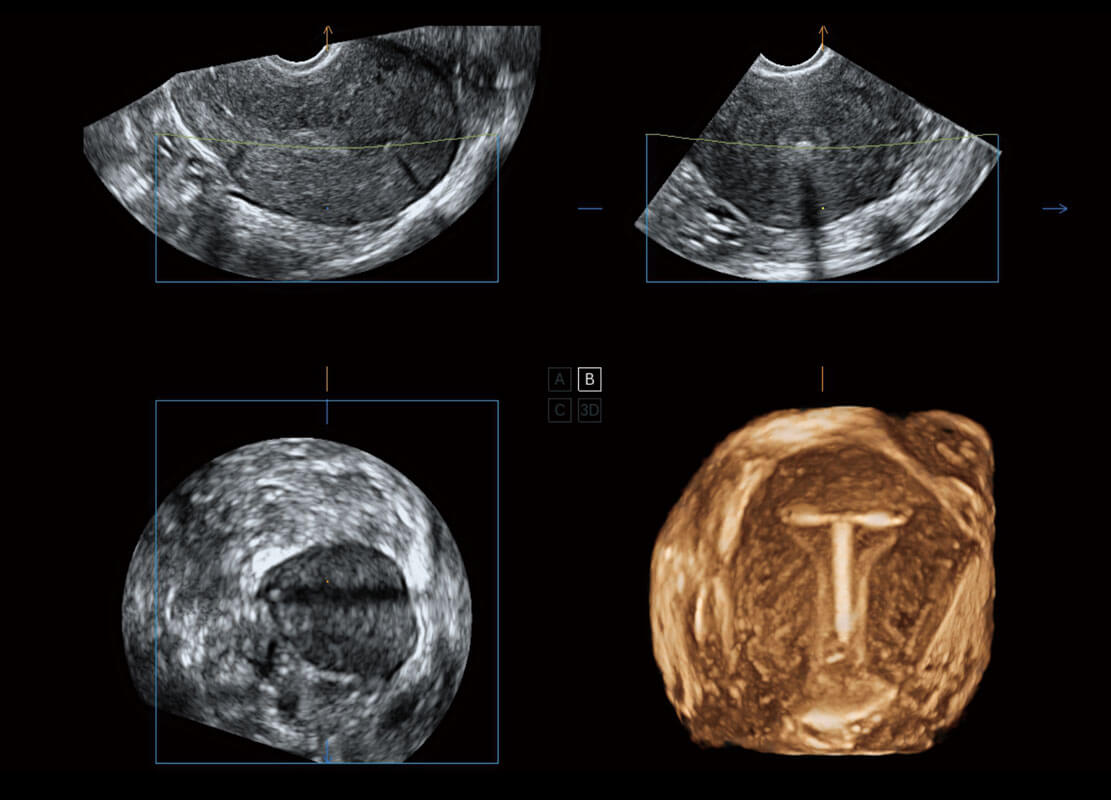

腔内三维-宫内节育器

腔内三维-光影成像

P60为盆底超声检查提供应用方案,多种腔内及腹部容积探头提供从二维、三维到四维的优异图像品质,实时快速三维容积数据获取,专业的测量工具包等人性化设计,为超声医生诊断提供有力保障。

Lev.Hiat A-r: 16.33 cm2

Lev.Hiat H-r: 53.70 mm

Lev.Hiat W-r: 43.96 mm

Lt-LUG-r: 24.16 mm

Rt-LUG-r: 19.94 mm

能够简化盆底检查的操作流程,可在二维模式及三维成像模式下实现一键自动提取出标准切面、自动识别当前切面、自动测量,提升盆底检查的高效性,同时也能让青年医生快捷的获得准确的检查结果。